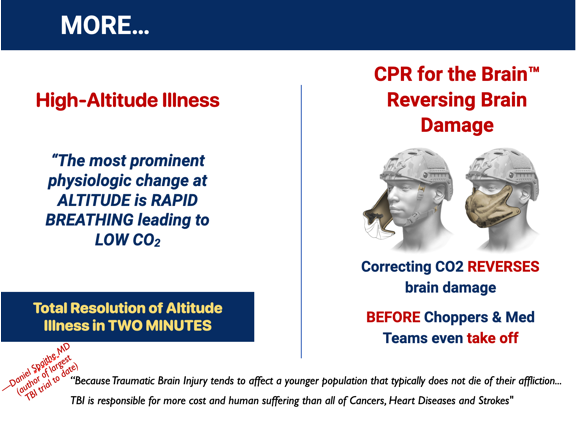

Altitude Illness, and

Reversing Brain Injury

So, what is the underlying problem? LOW CO2 appears as the common irregularity among the conditions above; another 15+ conditions show the same underlying cause. The solution clearly requires a means of elevating the body's CO2 level safely, conveniently, and inexpensively. From reviewing existing Sleep Apnea research and from several of our own lab studies, we believe the single solution for multiple adverse health conditions lies with elevating the body's CO2 level. DrDave™ Smith found a clever way to accomplish this while meeting the specified requirements: The SAGE Rebreather™ mask. And here's how it works...

Our SAGE Rebreather opens the door for making life better for millions. Our platform technology appears to be able to overcome 15+ adverse human conditions measuring in excess of 2 billion people worldwide. Here are the numbers we've been able to find for just the first three use-cases...